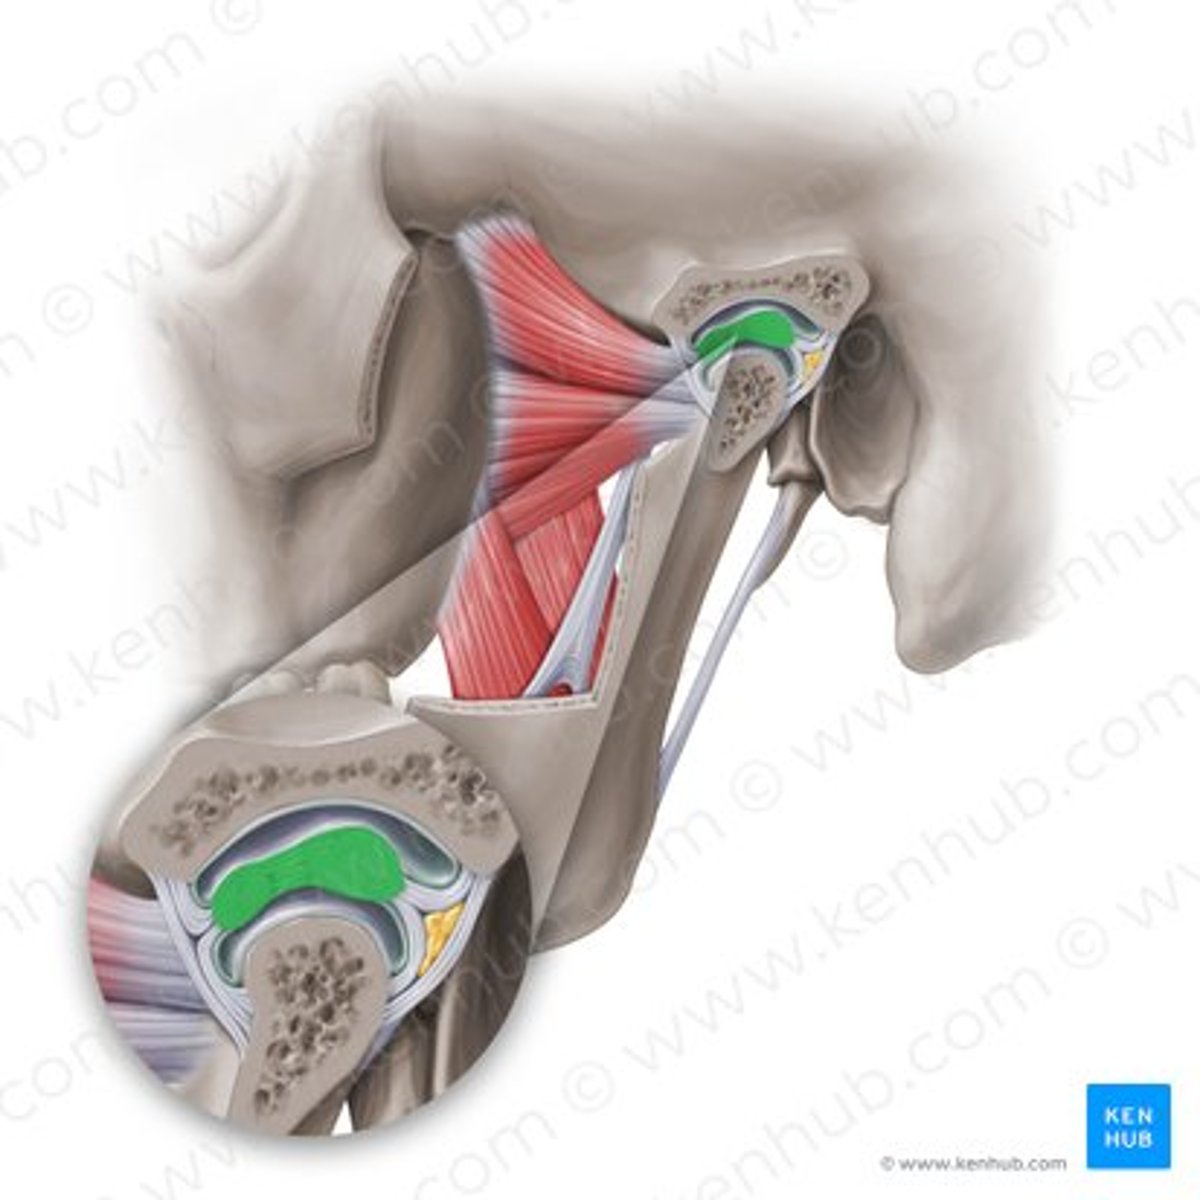

lateral pterygoid, superior part

lateral pterygoid, inferior part

articular tubercle

head of mandible

articular disk

joint capsule